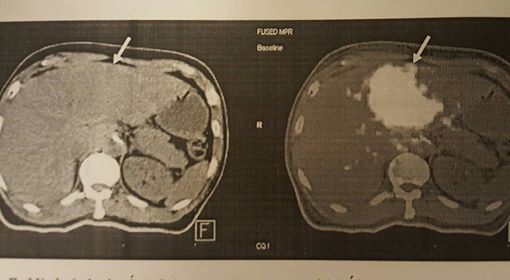

Trong đó, phương pháp nút mạch bằng hạt vi cầu phóng xạ là một phương pháp mới, đã được triển khai thành công ở Việt Nam 2 năm nay với 65 ca bệnh thành công ở cả 3 Bệnh viện Bạch Mai, BV Trung ương quân đội 108 và Chợ Rẫy.

“Khối u trong gan được nuôi dưỡng bởi các nhánh động mạch gan (90%), vì thế, phương pháp này sẽ bơm các hạt vi cầm phóng xạ trực tiếp vào động mạch nuôi khối u. Theo đó sẽ làm tắc mạch, làm xơ các đường dinh dưỡng truyền nuôi u và phát ra bức xạ tiêu diệt tế bào ung thư mà ít ảnh hưởng đến tế bào lành”.

TS Khoa cho biết, là một kỹ thuật cao, chi phí tốn kém (300 - 400 triệu đồng) nên chỉ định của kỹ thuật rất nghiêm ngặt. Thường ở bệnh nhân đã thất bại với các phương pháp điều trị trước đó (phẫu thuật, nút mạch nhưng vẫn thất bại, khối u to quá không thể phẫu thuật)... Hay có những bệnh nhân can thiệp nội mạch 7 - 10 lần, hiệu quả thấp và chi phí cao và nhiều lần can thiệp nội mạch sẽ dẫn đến teo gan, mất chức năng gan và không thể kéo dài thời gian sống thêm cho bệnh nhân. Lúc này, phương pháp nút mạch bằng hạt vi cầu phóng xạ sẽ tạo thêm cơ hội chữa trị cho bệnh nhân. Hiện nay, một số bệnh nhân ở giai đoạn sớm cũng chọn làm phương pháp này đầu tiên, bước đầu cho hiệu quả kiểm soát bệnh tốt, kích thước khối u giảm.